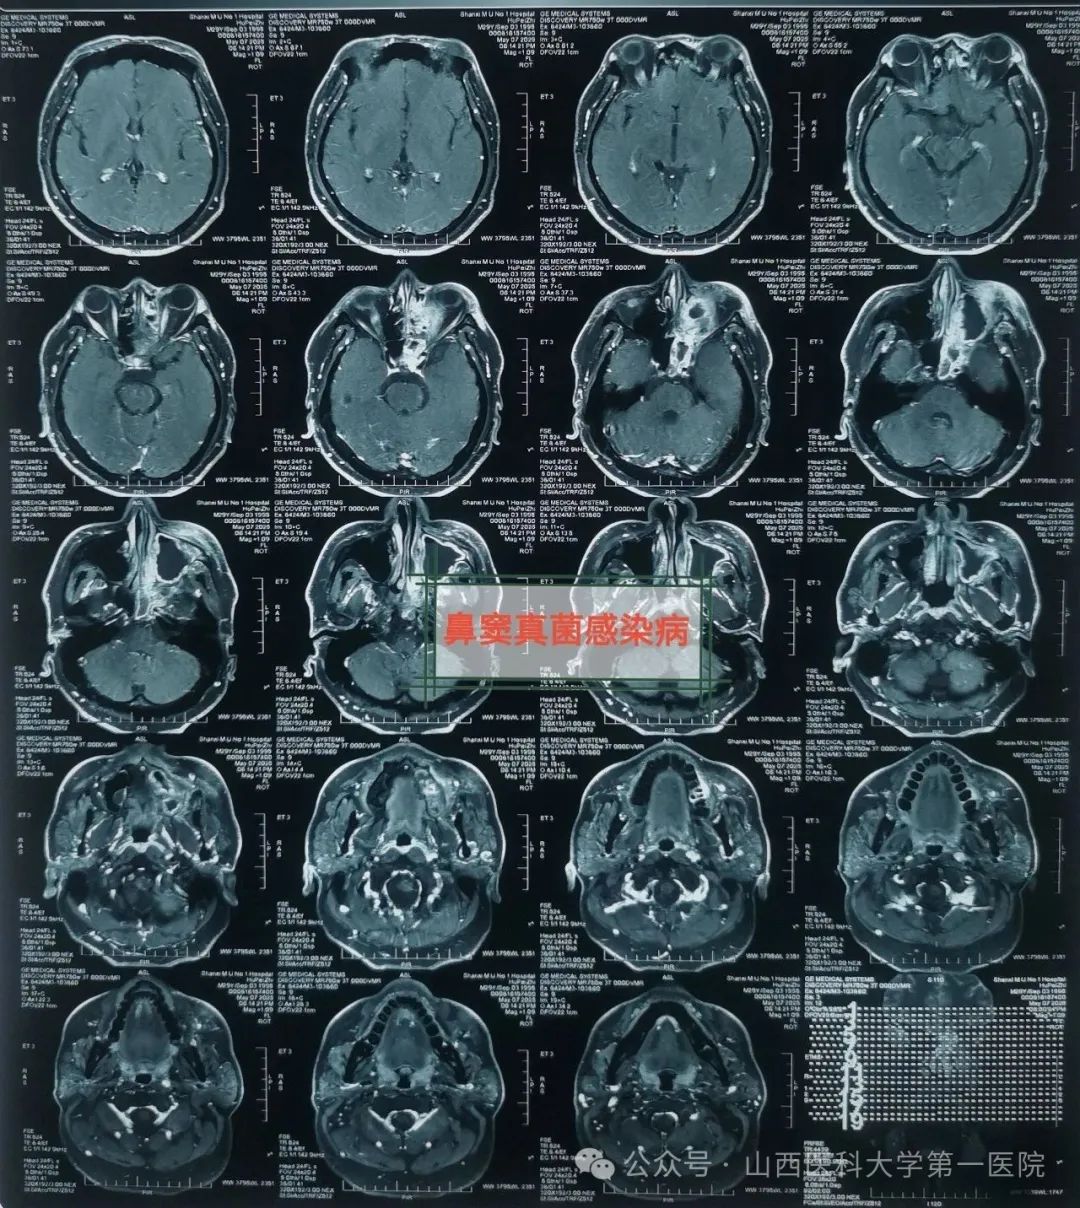

49岁的袁先生过敏性鼻炎多年,合并糖尿病与痛风,一直药物维持治疗;2年前因合并鼻窦炎,口服药物治疗效果不佳;近数月以来病情逐渐加重,鼻塞流涕,最近头痛头闷症状越来越严重同时出现鼻涕带血丝,就诊于51风流

耳鼻咽喉-头颈外科,确诊为鼻窦真菌感染,医生通过手术切除鼻腔病变组织,清除霉菌团块,开放鼻窦,引流分泌物,清洗术腔,重建鼻腔结构、恢复功能,改善并缓解了临床症状。

皇甫辉讲到,低免疫功能、低氧及高血糖环境是真菌生存合适条件,局部因素也是部分真菌性鼻窦炎主要致病因素之一,各因素所致鼻腔鼻窦通气引流受阻,解剖因素如中鼻道狭窄、中鼻甲反向偏曲等,局部炎症水肿,窦腔分泌物潴留,同侧上列牙齿病变等。真菌性鼻-鼻窦炎侵袭型者一经确诊,应尽早手术,清除鼻腔和鼻窦内真菌病原和坏死及不可逆之病变组织,恢复鼻腔鼻窦通畅引流,病变范围广者可采用柯-陆氏手术、与鼻内镜手术联合等术式,病变累及颅内时可采用颅面联合术式,术前应用抗真菌药物治疗,术后可应用抗真菌药物冲洗鼻腔和鼻窦等。